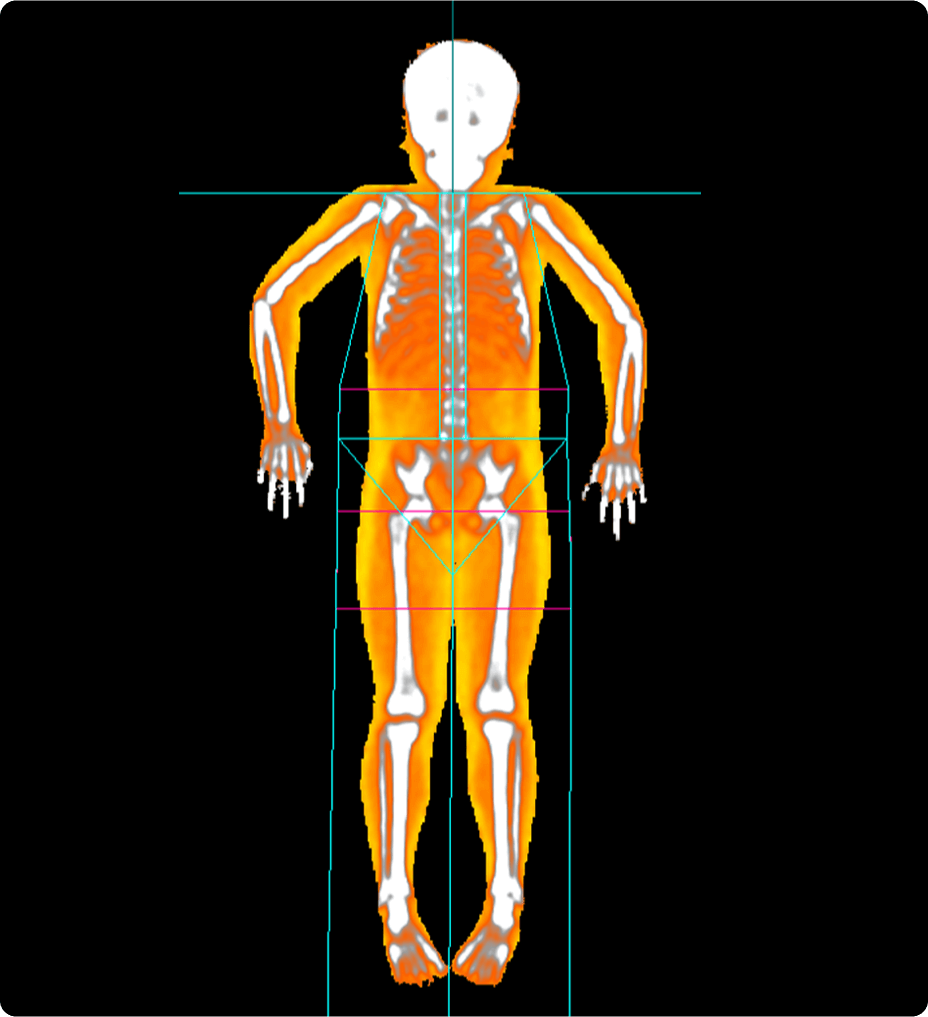

Améliorez votre qualité d’image IRM avec la technologie de reconstruction AIR™ Recon DL

Une meilleure imagerie, tout simplement